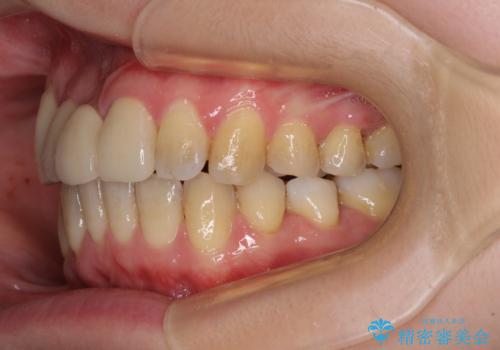

- 転倒により前歯の一部が欠けてしまったとのことで来院された患者様です。

神経が保存できる歯、神経を除去しなければならない歯、抜歯が必要な歯があり、ブリッジやインプラントなどによる治療を提案しました。

元々歯並びが気になっていたとのことで、前歯の治療を行うことを契機に矯正治療も行うこととしました。

本来であれば積極的に小臼歯を抜歯して口元を下げても良いのですが、前歯を1本抜歯しないといけなくなったため、非抜歯矯正をインビザラインを用いて行うこととしました。

補助装置により上顎歯列を遠心移動させたため、非抜歯でしたが口元の突出感をある程度改善させることができました。